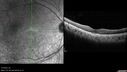

BRAO - plaques in vessels - GIF video of FA3 views78 year old female with vision loss for 1 week and old macular scar. Images show BRAO with plaques and FA shows occlusion.Oct 13, 2025

BRAO - plaques in vessels - GIF video of FA2 views78 year old female with vision loss for 1 week and old macular scar. Images show BRAO with plaques and FA shows occlusion.Oct 13, 2025